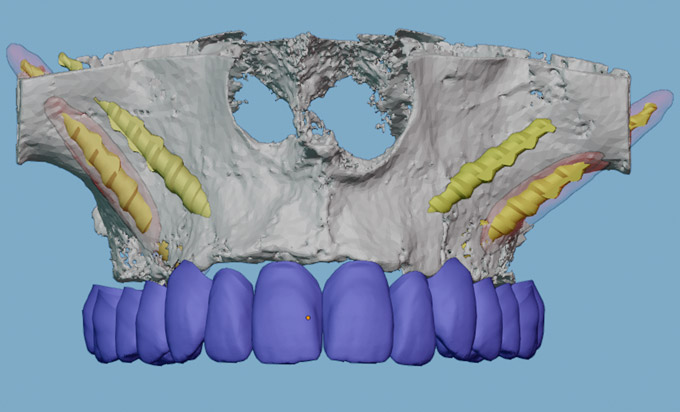

En casos complejos, tras resecciones oncológicas o por atrofias severas del maxilar, utilizamos los implantes cigomáticos para devolver al paciente su sonrisa. Estos tienen una longitud mayor que nos permiten posicionarlos en los huesos malares de la cara.

Ante la ausencia del hueso necesario para colocar implantes dentales utilizamos técnicas avanzadas de regeneración ósea para aportar soluciones a tus necesidades. Consigue tus dientes en una sola sesión gracias a la Cirugía Guiada y la tecnología de impresión 3D y el escáner intraoral.